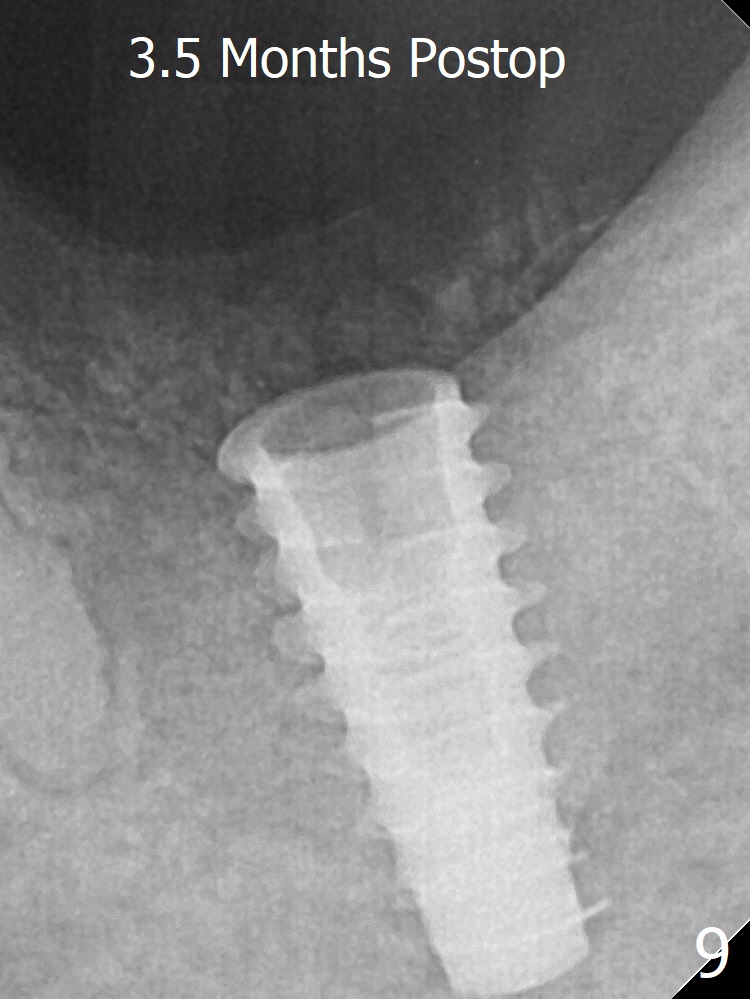

The implant seems to remain non-osteointegrated 3.5 months postop (Fig.9).  Later a 6.8x4 mm healing abutment is placed with occlusal clearance.  X-ray will be taken every 2-3 months until osteointegration occurs.